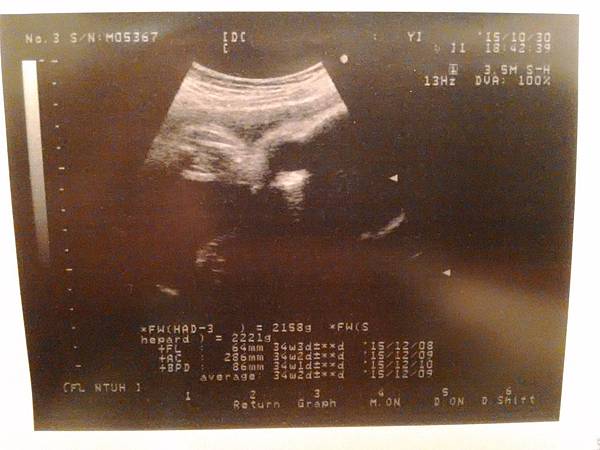

2015.10.30(五)

這次產檢,剛好遇到醫師接生,還好不會等太久~

婦產科醫師太辛苦了,很感恩他們的付出!